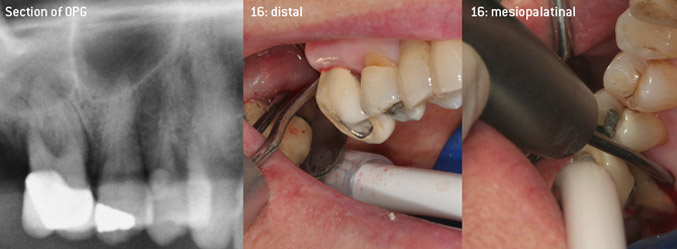

Come pionieri dello sviluppo della nuova punta per ablatori 3AP diamantata, i due dentisti hanno riconosciuto la necessità di migliorare le restrizioni di manipolazione delle punte diamantate disponibili in commercio, specialmente durante il trattamento della forcazione e lavorando su tasche intraossee strette. Tutto ciò deve essere fattibile sia per procedure non chirurgiche (figura 2) sia per procedure chirurgiche (figura 3).

(Foto (figure 2-4): © Dott. Christian Graetz)

L'idea era di sviluppare una punta applicabile universale al fine di evitare le sostituzioni della punta, per cui era richiesto parecchio tempo. Inoltre, si doveva facilitare l'utilizzo delle nuove punte in tasche intraossee strette dalla parte distale e all'entrata della forcazione distale dei molari mascellari, per consentire così un utilizzo più efficace degli strumenti. Ciò è stato possibile adottando una curva dello strumento con un diametro più ampio (figura 1), un vantaggio enorme in particolare per il debridement chiuso sui denti con perdita avanzata degli attacchi e dove entra in gioco la forcazione (figura 4).